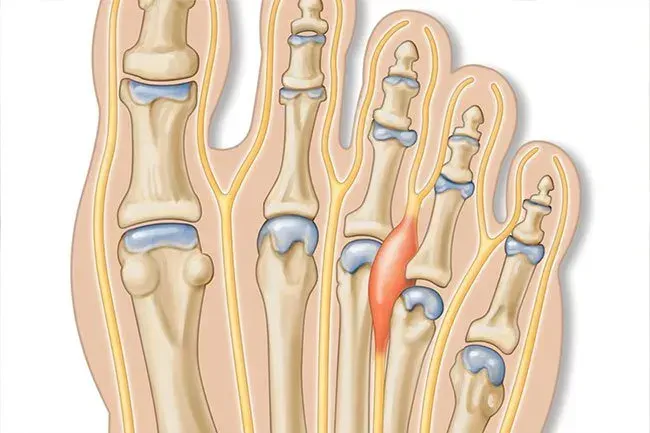

Mortonův neurom

Toto je velmi běžný stav nohou. Může to mít až jeden ze tří lidí. Mezi příznaky patří bolest v přední části vaší nohy nebo pocit, jako byste chodili po skále nebo mramoru. Stává se to častěji u starších žen a u těch, kteří nosí vysoké podpatky nebo boty s těsnou krabicí na špičce. Přepínání obuvi obuvi a masáž může pomoci. Pokud se vaše bolest váží, může váš lékař navrhnout výstřely nebo chirurgický zákrok.